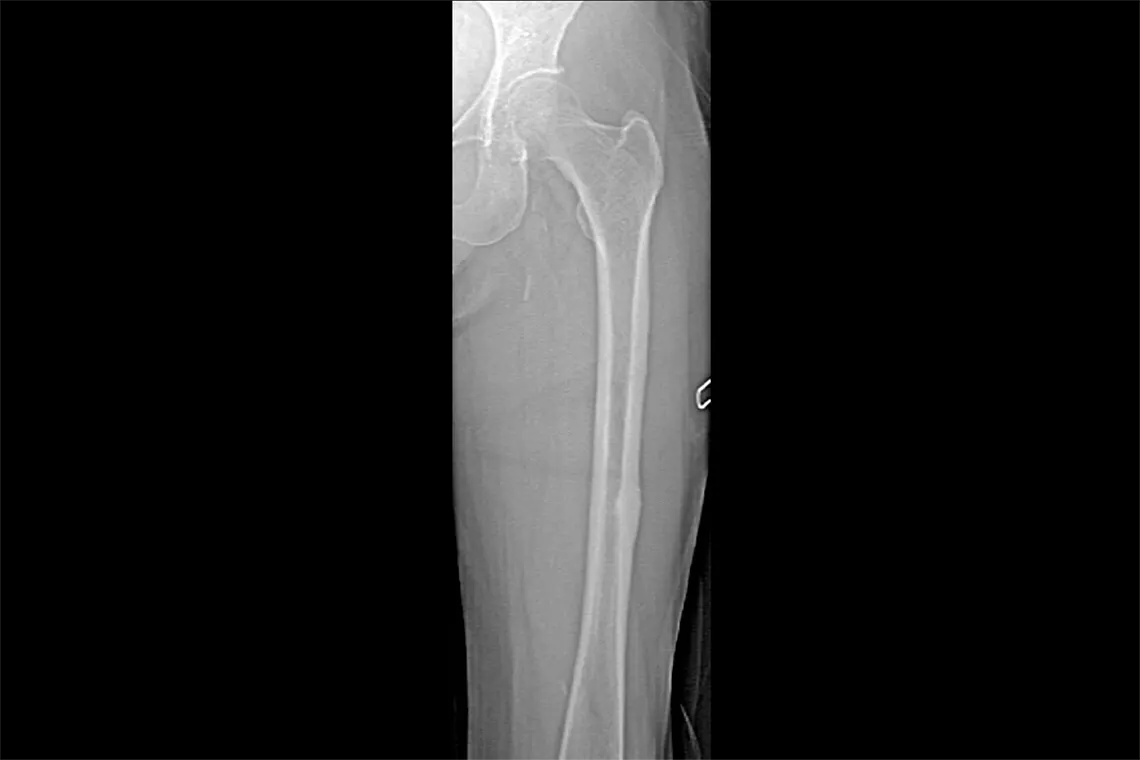

Horizon DXA produces radiographic quality images of the entire femur for assessment of potential atypical femur fractures.31 A quick, 15-second scan reveals cortical thickening of the bone, making it fast and easy to monitor the effects of bisphosphonate therapy over time.